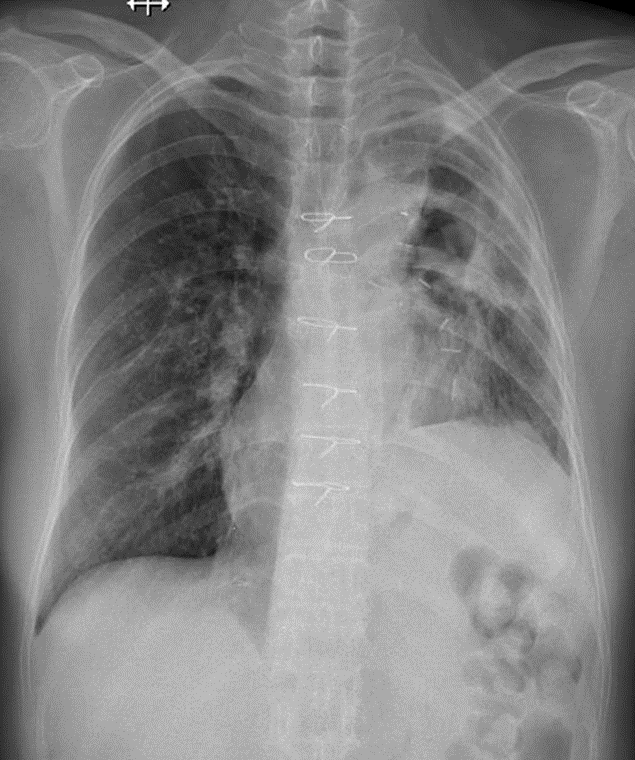

1-Thâm nhiểm phế nang lan tỏa phổi (T) => Viêm phổi 2-Tràn dịch màng phổi thể hoành 3-Cung động mạch chủ đóng vôi 4-Chỉ kim loại thành ngực dọc xương ứng 5-Chỉ kim loại ngực (T) sau phẫu thuật phổi